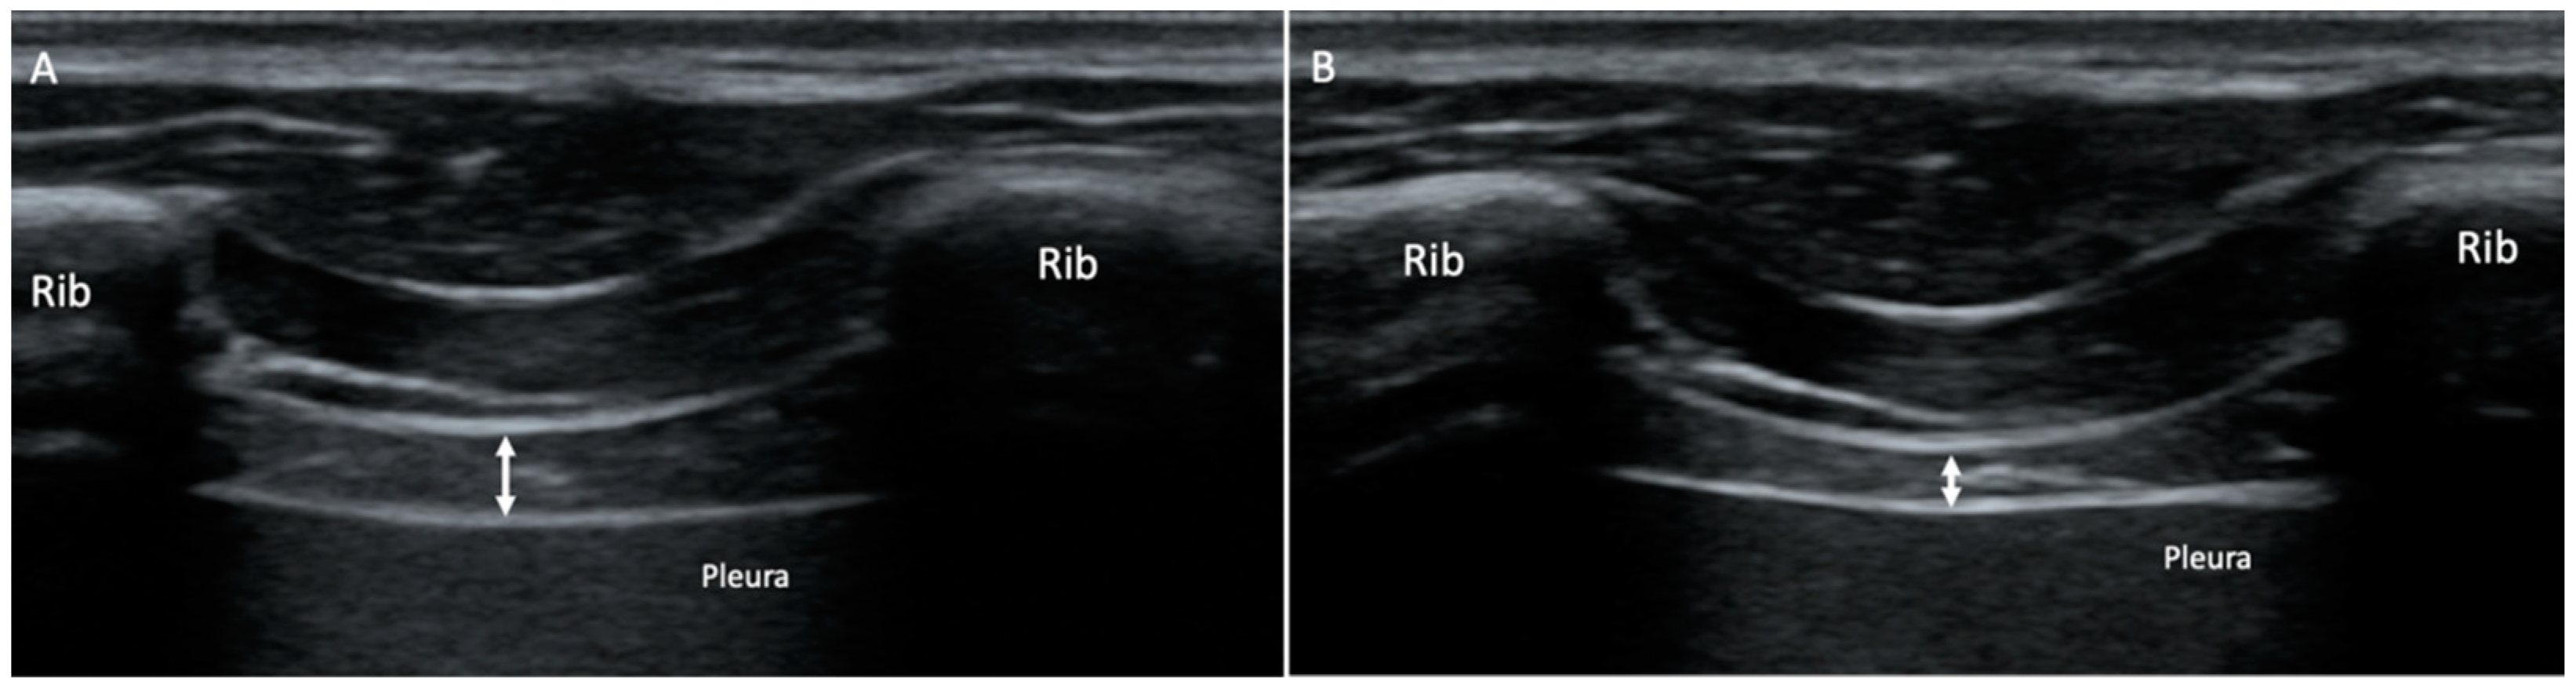

- Marugán-Rubio, D.; Chicharro, J.; Becerro-de-Bengoa-Vallejo, R.; Losa-Iglesias, M.; Rodríguez-Sanz, D.; Vicente-Campos, D.; Dávila-Sánchez, G.; Calvo-Lobo, C. Concurrent Validity and Reliability of Manual versus Specific Device Transcostal Measurements for Breathing Diaphragm Thickness by Ultrasonography in Lumbopelvic Pain Athletes. Sensors 2021, 21, 4329. [Google Scholar] [CrossRef]